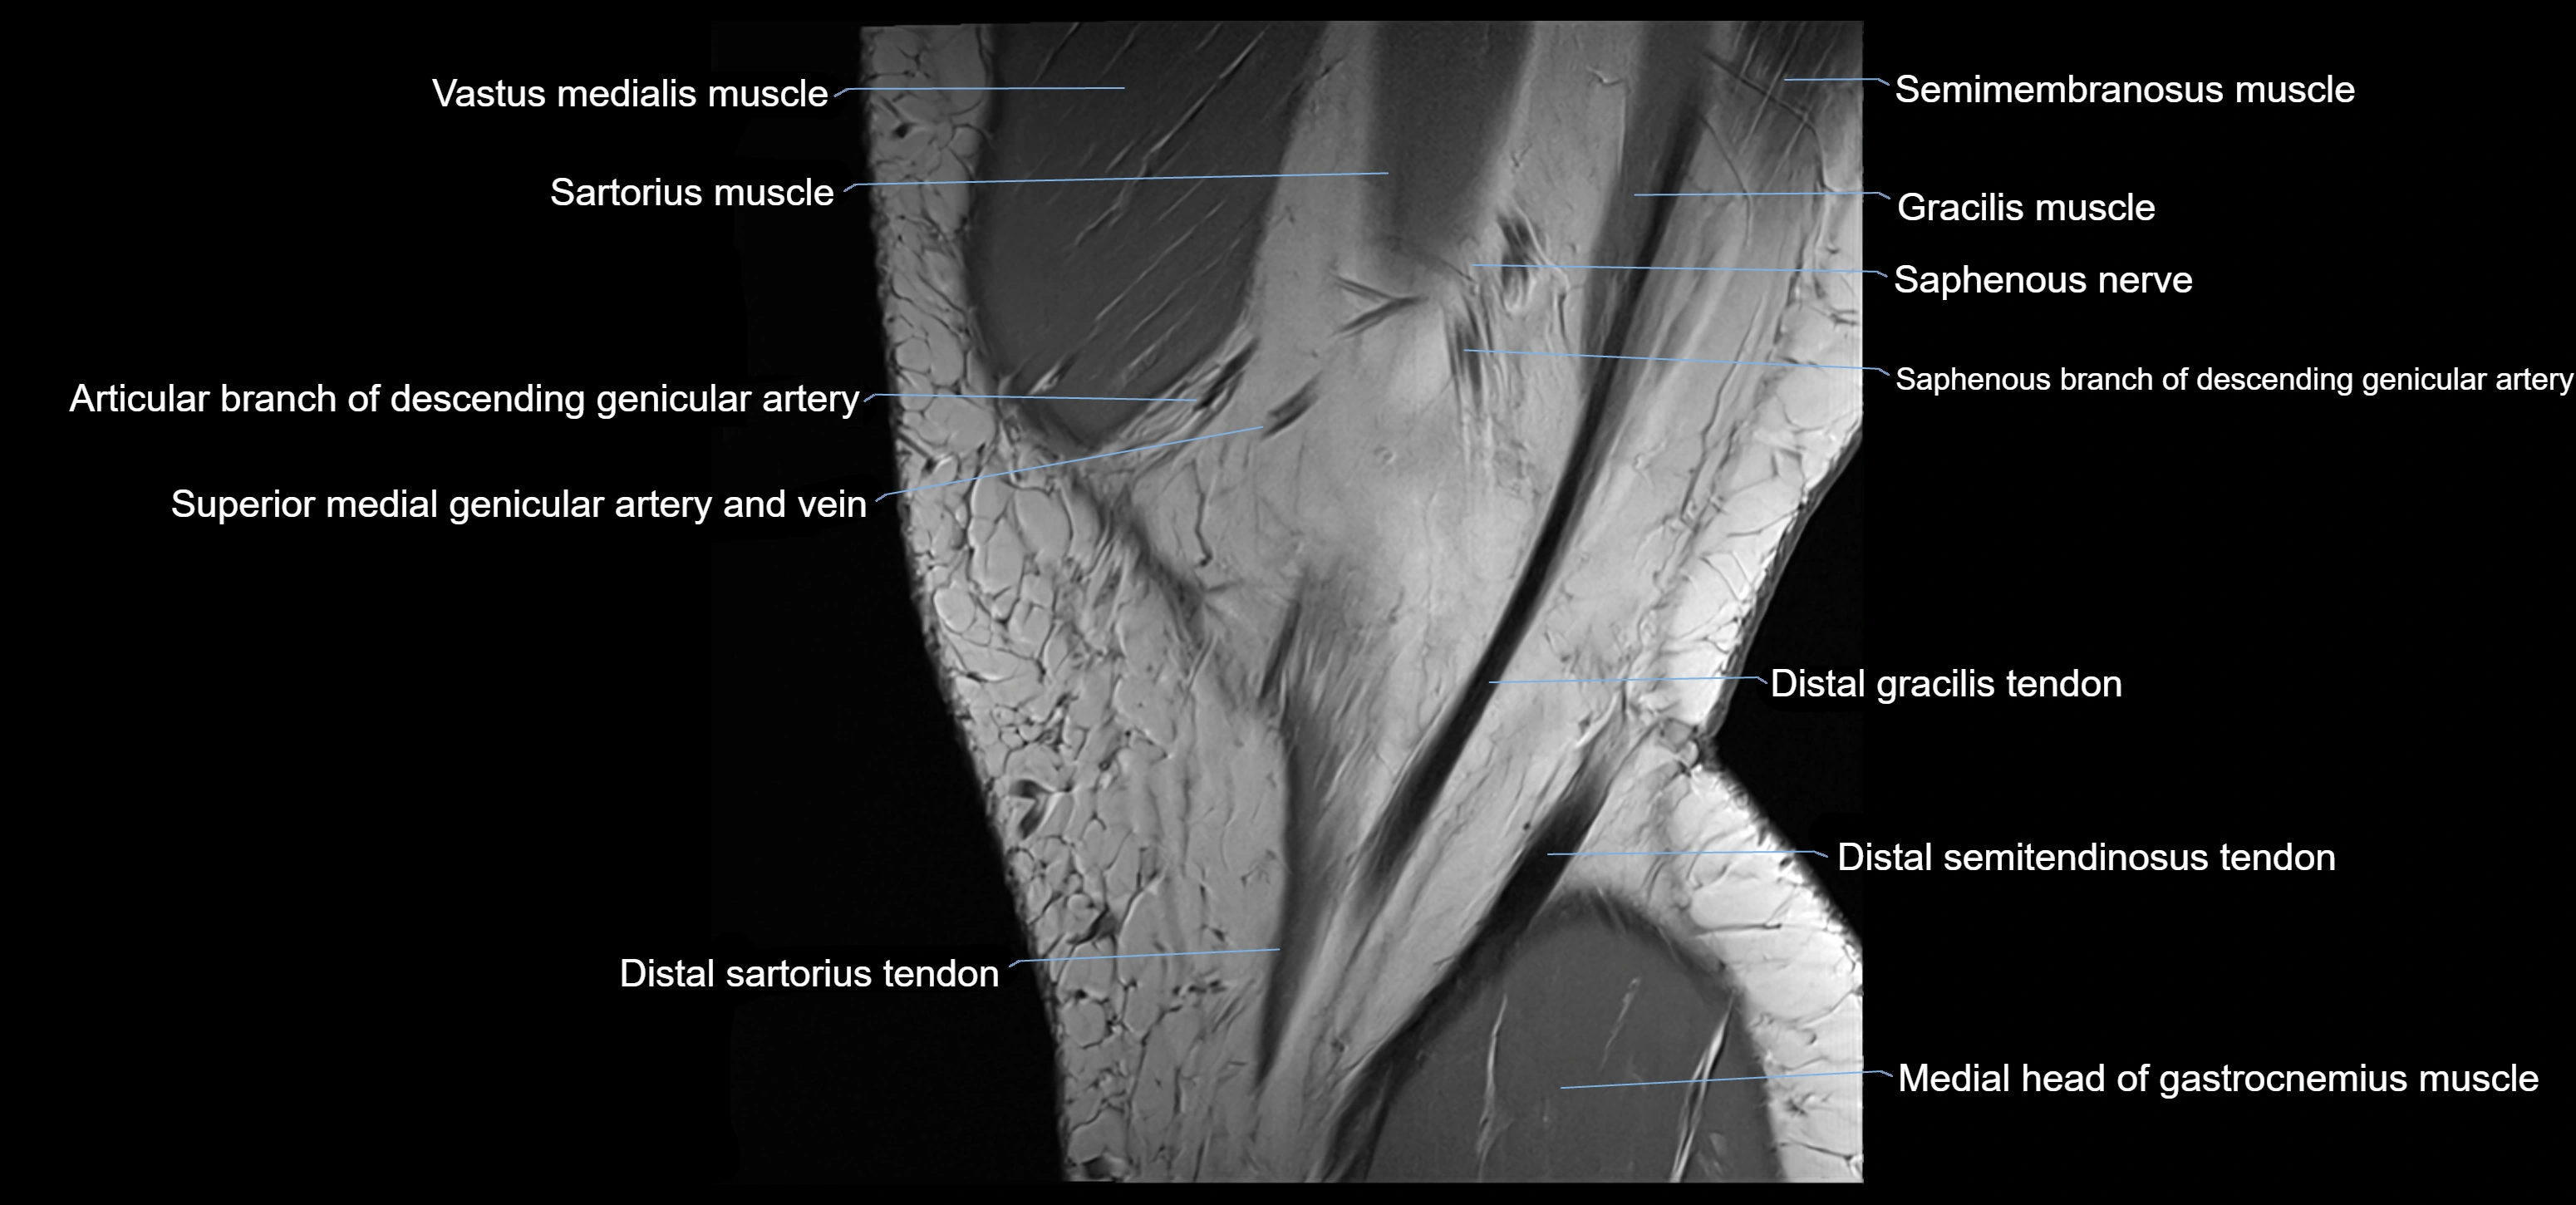

- Descending genicular artery (Articular branches)

- Descending genicular artery (Saphenous branch)

- Distal semitendinosus tendon

- Gracilis Tendon (Proximal)

- Gracilis tendon (Distal)

- Medial gastrocnemius tendon

- Medial head of gastrocnemius muscle

- Saphenous nerve

- Sartorius muscle

- Sartorius tendon (Distal)

- Semimembranosus muscle

- Semitendinosus muscle

- Superior medial genicular artery

- Superior medial genicular vein

- Vastus medialis muscle